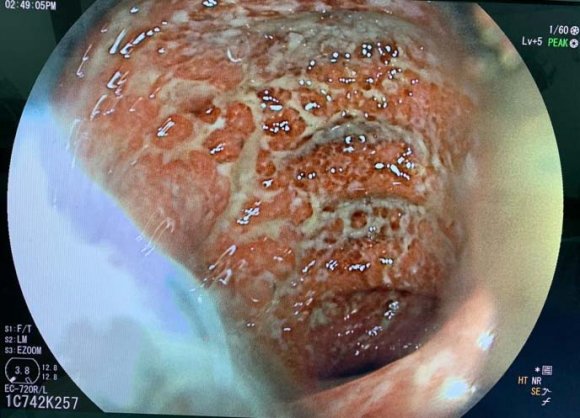

The patient was admitted again 6 months later, she developed bloody diarrhea with abdominal pain, and tenesumus, colonoscopy revealed inflamed hyperemic colonic mucosa with multiple active ulcers, Hemoglobin (Hb) was 9.1 g/dl (normocytic), white blood cell count was 12.44 × 103/ml (neutrophilic leukocytes: 90.8%, lymphocytes: 7.4%), and platelets were 3 × 105 /?l, C-reactive protein(CRP) and erythrocyte sedimentation rate were 78 mg/dl and 35 mm/h respectively. The patient was therefore treated with intravenous corticosteroids (1mg/kg/day) for 7 days then with PSL 50 mg/day, and azathioprine was switched to 6 mercaptopurine (6MP) 75mg/day, this was followed by clinical and biological improvement.

A year and two months later, the patient was admitted for an UC attack, she was having Bloody diarrhea as well as severe tenesmus and rectal bleeding, colonoscopy revealed inflamedfriable mucosa severely hemorrhagic. Bblood test reveled anemia with Hb: 8.4 g/dl (normocytic), white blood cell count was 15.333 x 10 3 /ml, CRP was 120 mg/dl, stool studies were negative for infection. Intravenous corticosteroids as well as corticosteroid and 5-ASA enemas were begun and the patient showed clinical and biological improvement (number of bloody diarrhea diminished as well as CRP (40 vs 120). The colitis was then considered an immunomodulator refractory colitis, and we had to consider another treatment to maintain remission.